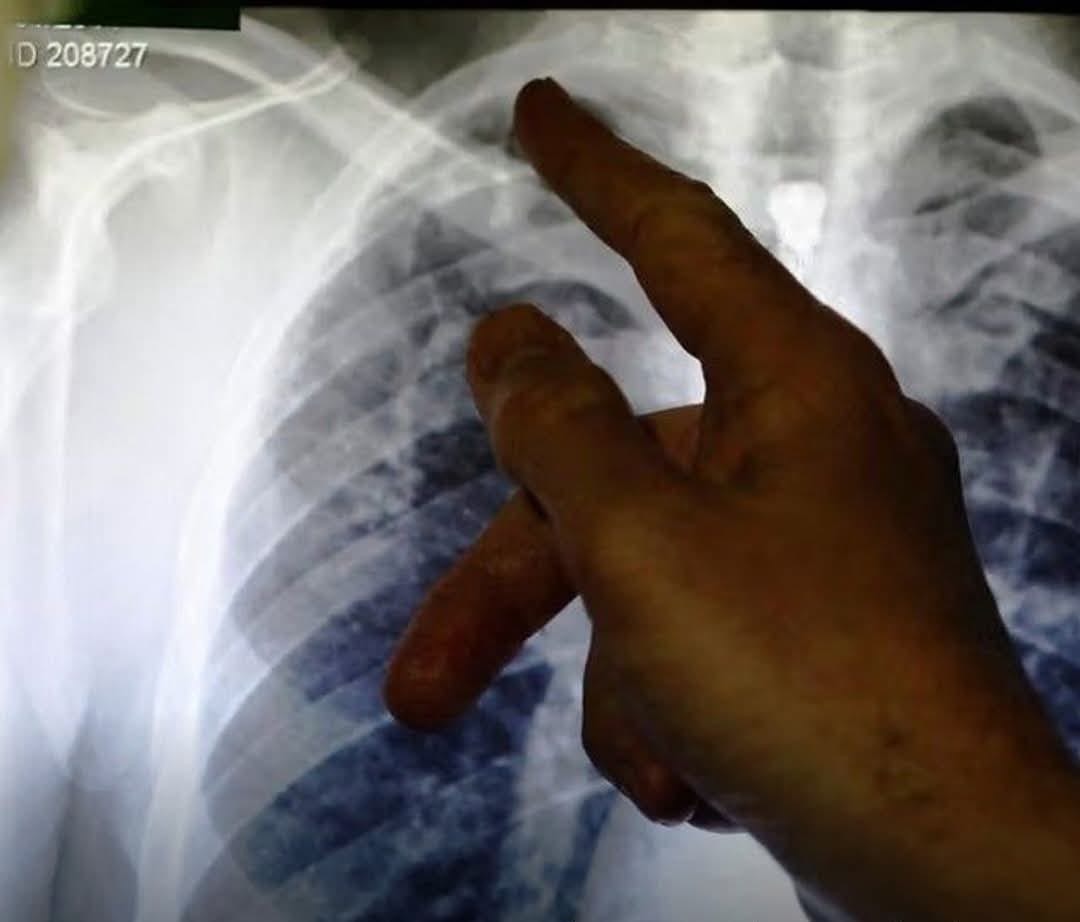

The World Health Organization (WHO) has announced on the occasion of World Tuberculosis Day that thousands of people in Afghanistan are infected with the disease every year.

Edwin Siniza Salvador, WHO Country Director for Afghanistan, also warned that tuberculosis remains a serious health threat in the country and requires urgent attention.

Unprecedented increase in tuberculosis among Afghan citizens in 2026